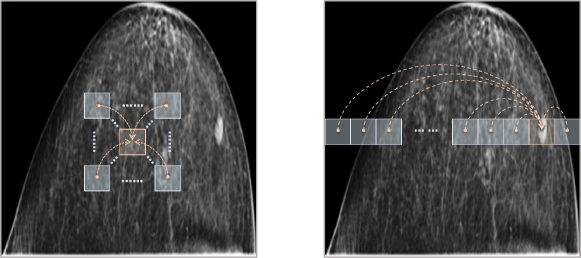

Refer to caption

Figure 3: Diagrams of local (left) and non-local (right) attention mechanisms on a CC view image.

Between these two simple solutions, we come up with a trade-off to alleviate the misalignment problem in dual-view mammograms. Instead of simply reducing the spatial dimensions, we introduce a local attention mechanism to make each pixel perceive its neighbors within a certain range, as shown in the left image of Fig. 3. Within the range, the misalignment has a chance to be corrected. That is, if it has a high possibility that a pixel FMLO(i,j)subscript𝐹𝑀𝐿𝑂𝑖𝑗F_{MLO}(i,j) corresponds to its counterpart around FCC(i,j)subscript𝐹𝐶𝐶𝑖𝑗F_{CC}(i,j), we relate it to its belonging local patch {FCC(i+θ,j+θ),σ<θ<σ,σ>0}formulae-sequencesubscript𝐹𝐶𝐶𝑖𝜃𝑗𝜃𝜎𝜃𝜎𝜎0\{F_{CC}(i+\theta,j+\theta),-\sigma<\theta<\sigma,\sigma>0\}, where σ𝜎\sigma is the misalignment range, yielding a reinvented map RCC(i,j)subscript𝑅𝐶𝐶𝑖𝑗R_{CC}(i,j) (similar to RMLO(i,j)subscript𝑅𝑀𝐿𝑂𝑖𝑗R_{MLO}(i,j)). Hence, the reinvented features are more friendly to compute the dual-view correlation loss, since each pixel is already encoded with its neighbors, among which the corresponding pixel in another view can find its align one.

For pixels in each row across views, the misalignment range σ𝜎\sigma is hard to estimate, as implied in Fig. 2. To tackle this, we also introduce a non-local attention mechanism to have each pixel contain the entire information of its belonging row, as shown in the right image of Fig. 3. Combining both local and non-local attentions, the feature map extracted by the modified truncated ResNet101 is reinvented in a hybrid attention fashion. In the next subsection, we instantiate the hybrid attention as our proposed hybrid attention module and give details of its two key constitutions, i.e., local relation block and non-local attention block.